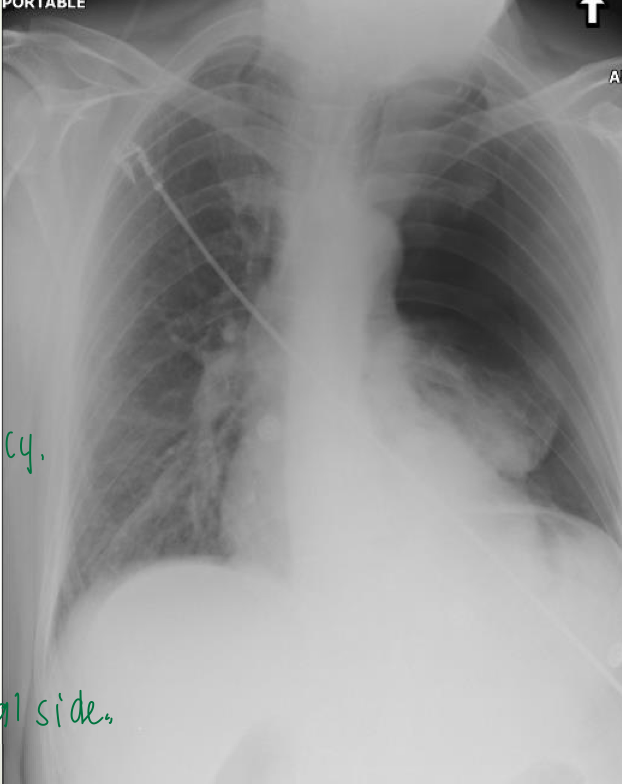

Hemodynamically

unstable, 35 yo

male with sudden

onset dyspnea and

chest pain 3 hours

ago.

what’s going on?

this is a major pneumothorax ont he left hand side. there is a completely black lung and hilum cannot be seen on left side. there is also a tracheal shift to the contralateral side. this is a tension pneumo